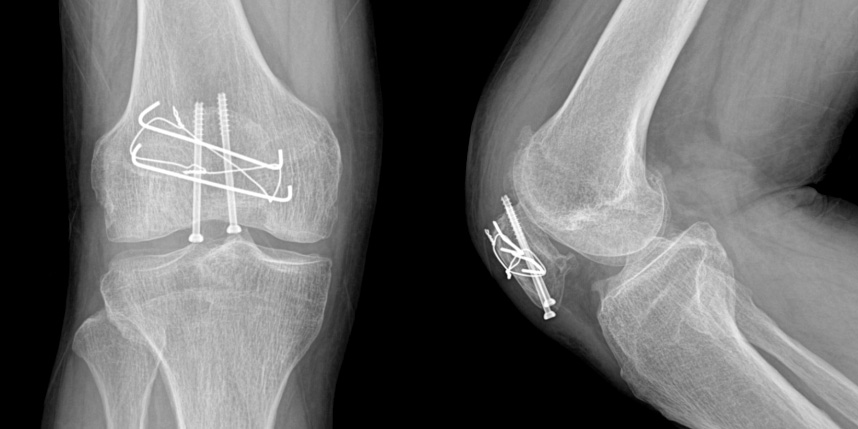

골절은 정확하게 골절편을 잘 맞추고 고정하는 것이 중요합니다. 특히 관절면을 잘 맞추는 것이 중요합니다.

또한 수술 이후 빠른 재활을 통해 전체적인 회복을 도모하여 일상으로 빨리 복귀할수 있도록 해야 합니다.

무릎 골절

* 환자에게 받은 소중한 자료입니다.